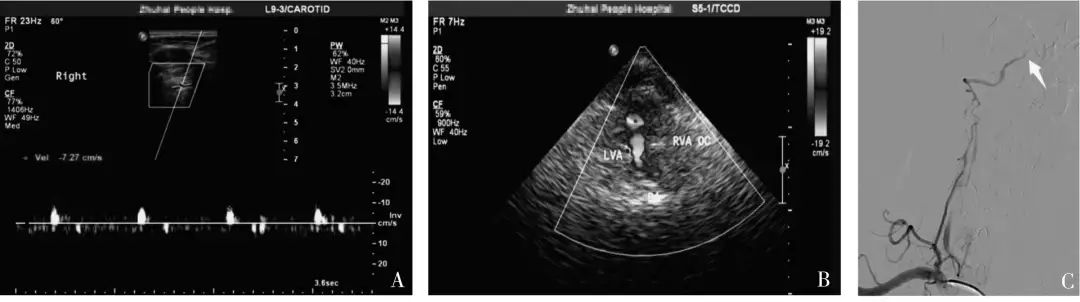

20199月,暨南大學(xué)附屬珠海醫(yī)院報道了一項研究[1],經(jīng)由CTADSA結(jié)果證實為單側(cè)椎動脈顱內(nèi)段閉塞患者40 例,由未規(guī)范培訓(xùn)組醫(yī)師和規(guī)范培訓(xùn)組醫(yī)師分別進行血管超聲檢查,將兩組超聲診斷結(jié)果與金標準結(jié)果進行比較,并對兩組不同資歷醫(yī)師進行診斷一致性分析。

結(jié)果:規(guī)范培訓(xùn)組診斷椎動脈顱內(nèi)段閉塞的敏感度及符合率(均為95%)明顯高于未規(guī)范培訓(xùn)組(均為75%),不同資歷的超聲醫(yī)師對于椎動脈顱內(nèi)段閉塞的一致性檢驗結(jié)果Kappa 值為0.273,診斷一致性較差。

中國腦卒中血管超聲檢查指導(dǎo)規(guī)范[2]指出:若椎動脈閉塞于小腦后下動脈分支之前,椎動脈顱外段可探及低速單峰型(無舒張期血流信號);若椎動脈閉塞于小腦后下動脈之后,椎動脈顱外段可探及低速高阻型(舒張期流速低平)血流信號。

本研究中,未規(guī)范培訓(xùn)組椎動脈椎間隙段頻譜形態(tài)呈“高阻型”10 例中,全部診斷為椎動脈發(fā)育不良,“單峰型”30 例全部診斷為顱內(nèi)段閉塞。

當(dāng)椎動脈椎間隙段內(nèi)徑≤2.5 mm,頻譜形態(tài)呈低速高阻型改變時,既有可能是椎動脈發(fā)育不良,也有可能是椎動脈顱內(nèi)段閉塞,此時應(yīng)聯(lián)合TCCS(或TCD) 檢查,直觀地從枕窗觀察雙側(cè)椎動脈顱內(nèi)段的血流充盈情況。